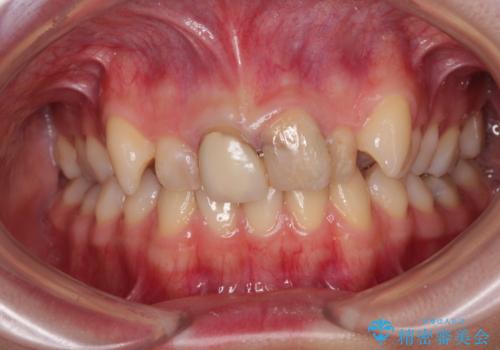

変色したバランスの悪い前歯をオールセラミッククラウンで自然な口元に

- 学生の頃に神経を取り除いた前歯の変色と、色合いの悪いかぶせ物が気になるとのことで来院された患者様です。

レントゲン写真より、歯根の炎症が認められず、土台もしっかりと植立されていたため、仮歯に置き換えた後にオールセラミッククラウンにて補綴することとしました。

当初は矯正治療を希望されていましたが、関西圏への転居と結婚式が間近であるということから、前歯の補綴治療のみを行うこととしました。